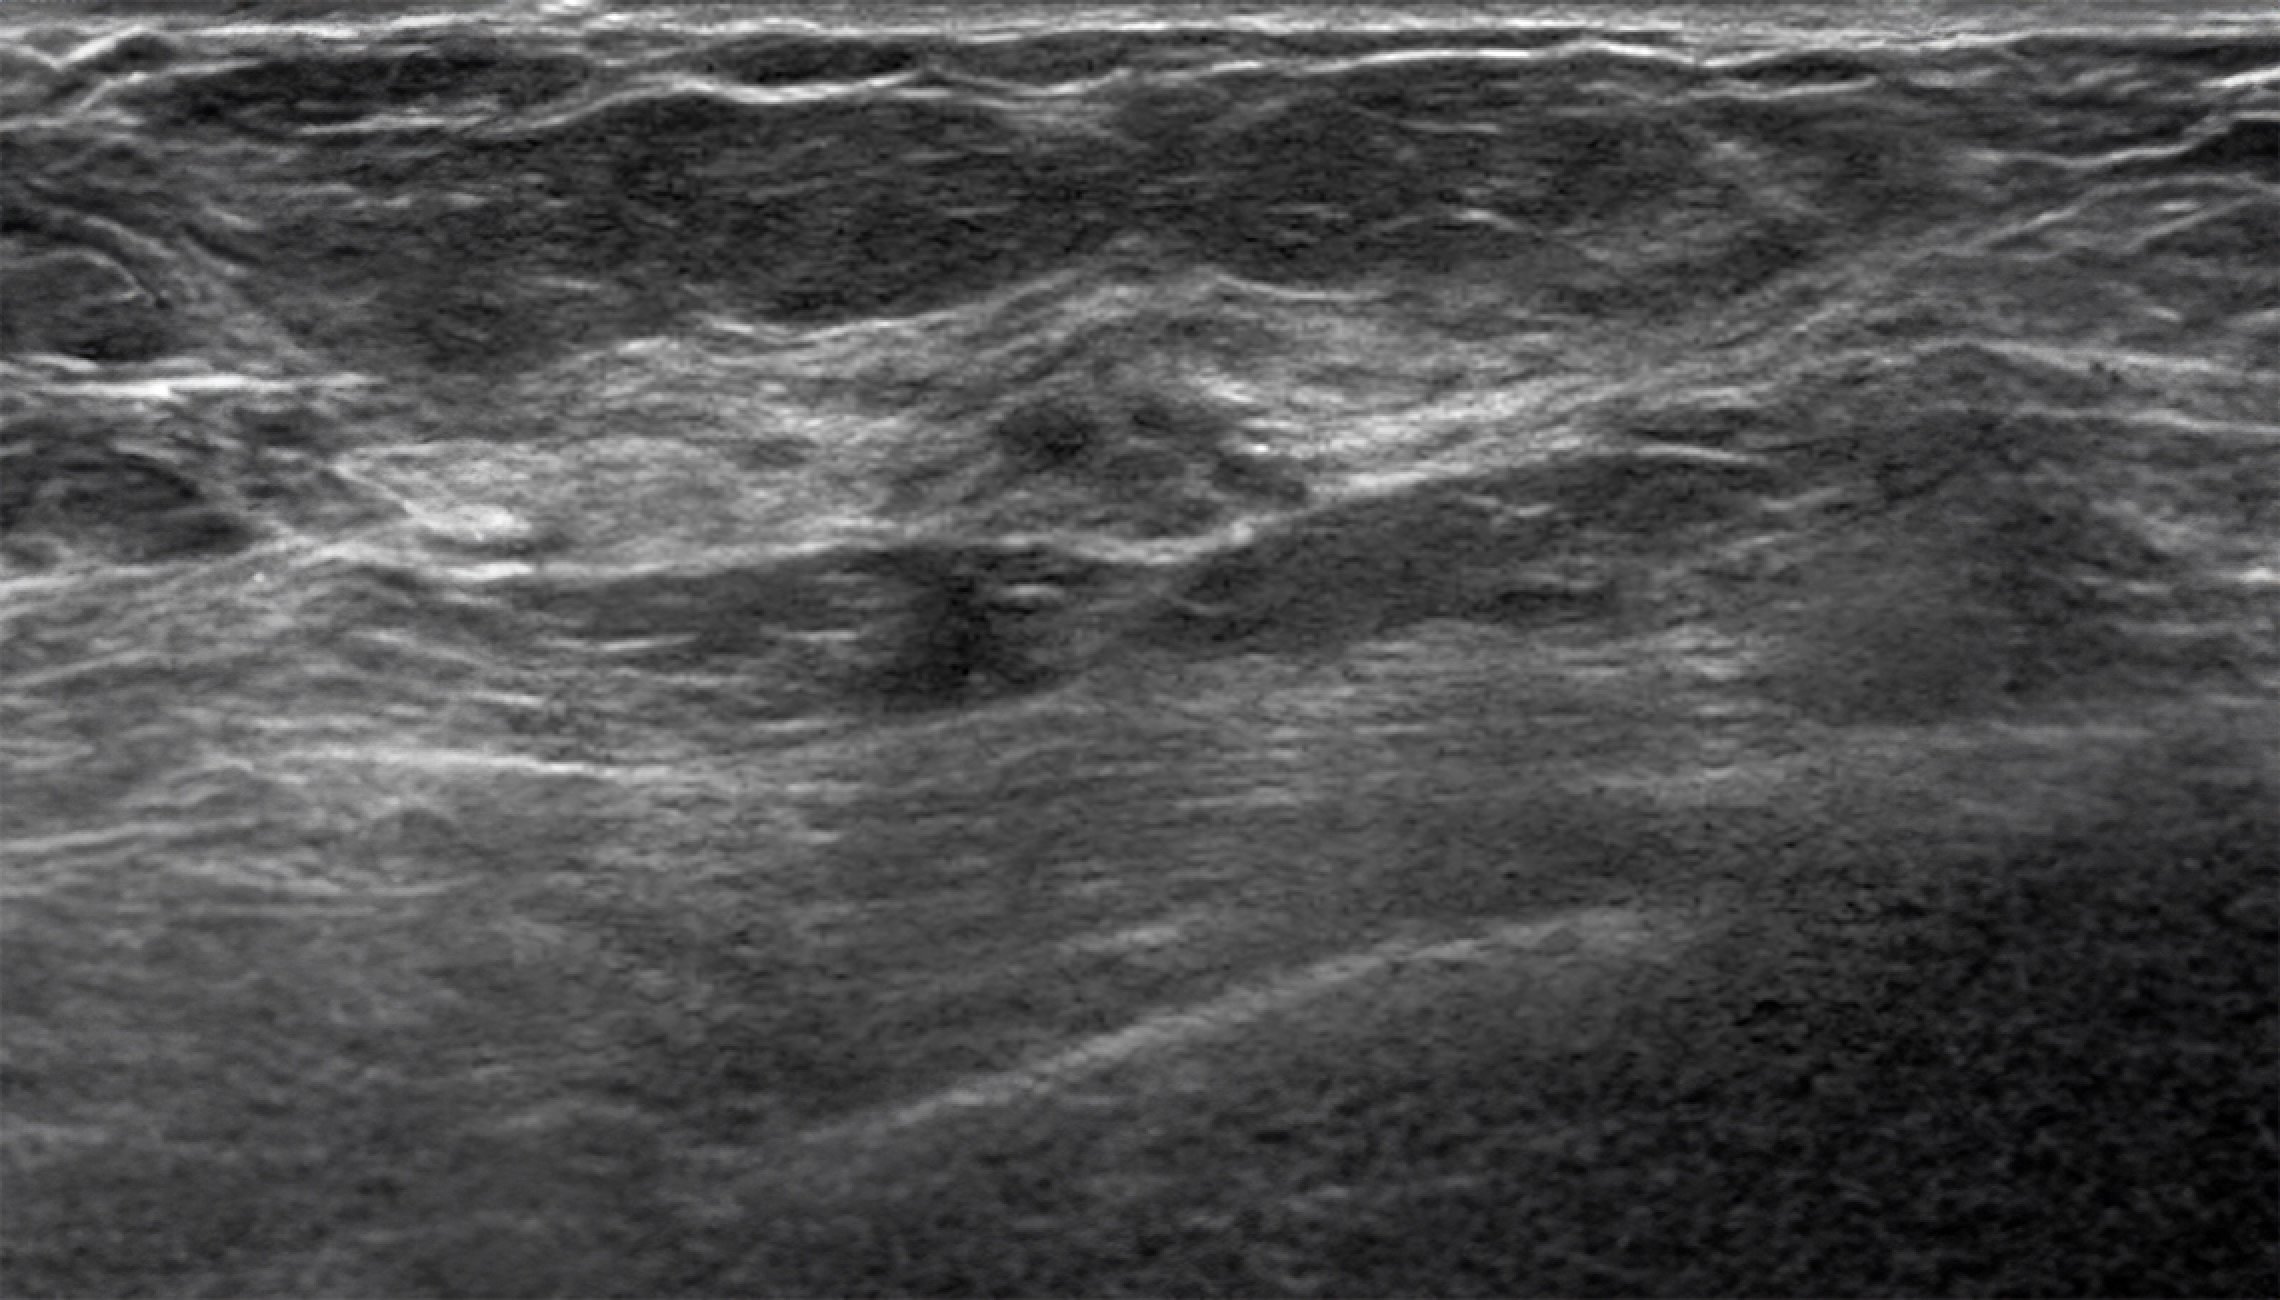

Follow up mode

Automatically matches lesions from previous breast ultrasound examinations, allowing for easy comparison of changes in the lesions.